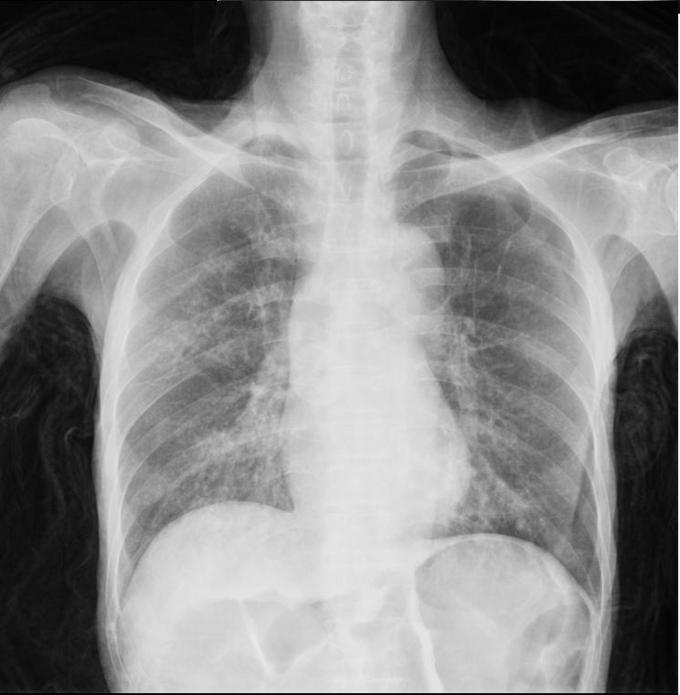

男性,61岁吞咽困难1月 进行性吞咽困难,无饮水呛咳,无发热,无咳嗽 咳痰

消瘦,双肺未闻及干湿性啰音。浅表淋巴结无肿大。

患者白日行钡餐检查,夜间出现呼吸困难,血氧饱和度下降,考虑存在1型呼吸衰竭 讨论: 1.目前针对钡餐误吸性肺炎的治疗措施哪些有意? 2.如何预防本次事件?